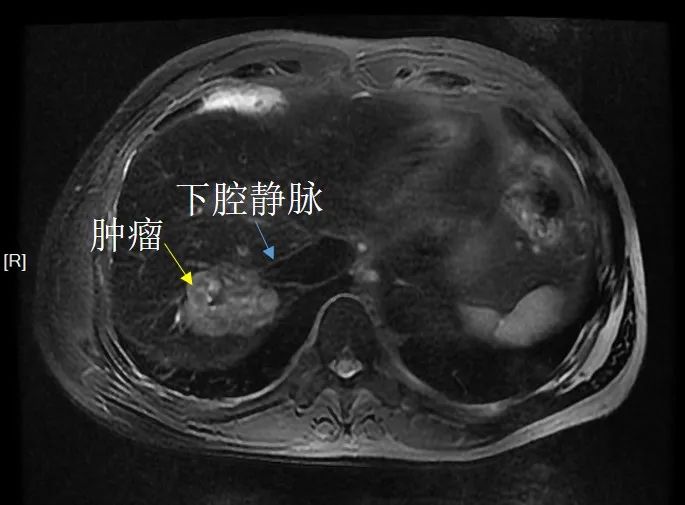

杜先生虽然是单发肿瘤,但肿瘤内缘已邻近下腔静脉,专家评估直接手术切除不能保证肿瘤内侧有效的切缘,不能作为首选方法。

治疗前,杜先生的肿瘤临近下腔静脉

经载药微球栓塞,肿瘤活性区域缩小,且边缘较治疗前远离下腔静脉。